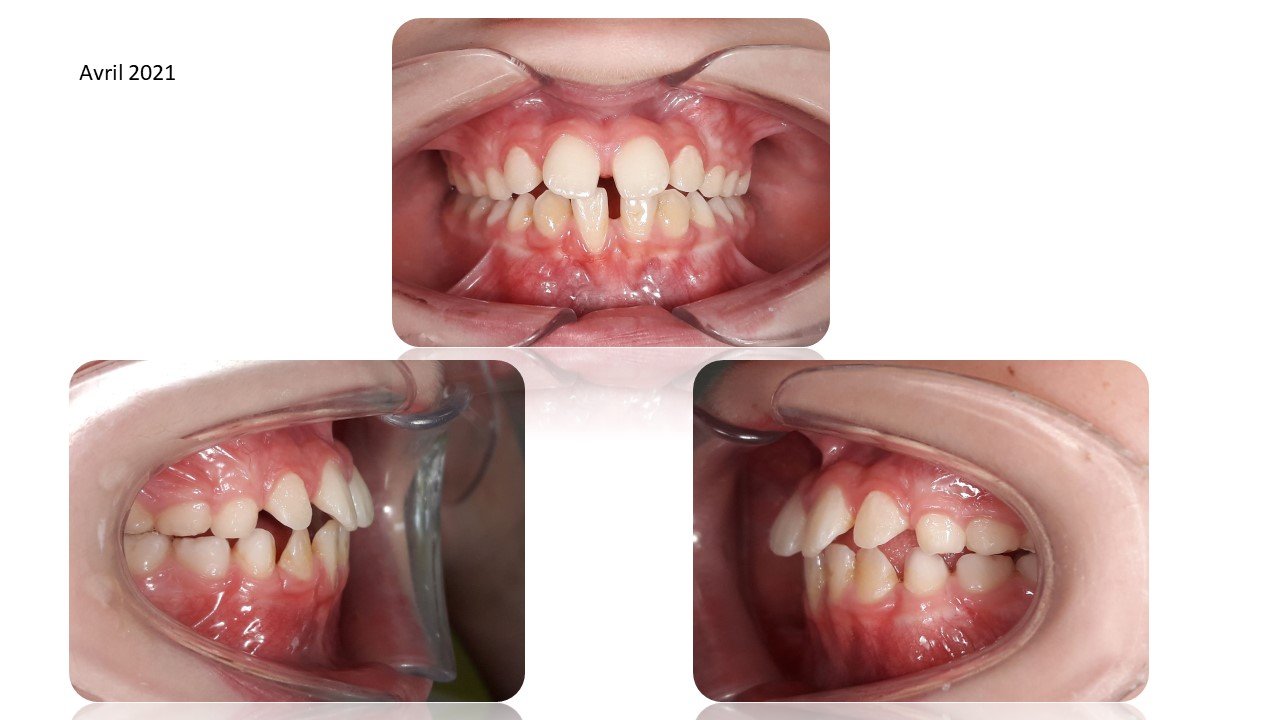

La Classe III Squelettiques

Les classes III squelettiques sont l’expression d’une orientation pathologique du plan occlusal et de la croissance faciale.

L’orthodontie systémique permet d’appréhender cette pathologie par l’analyse des latéralités mandibulaires.

Le traitement qui en découle est donc fonctionnel et stable car il permet non pas seulement une protraction du maxillaire mais une réorientation complète de celui-ci. Cette prise en charge permet de retrouver une proprioception maximale du prémaxillaire dans la mastication, gage de stabilité à long terme.